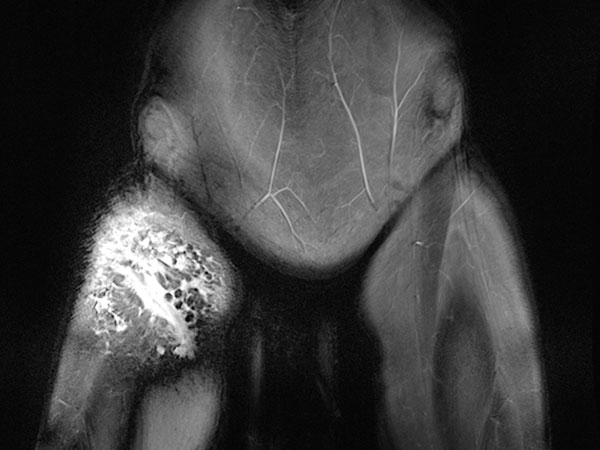

In der 3D-Darstellung der computertomographischen Angiographie findet sich ein normaler Befund der rechtsseitigen Arterien und Venen der Leiste und des Oberschenkels. Diese sind nicht an der Malformation beteiligt. Auch die darunter liegenden knöchernen Strukturen sind unauffällig.